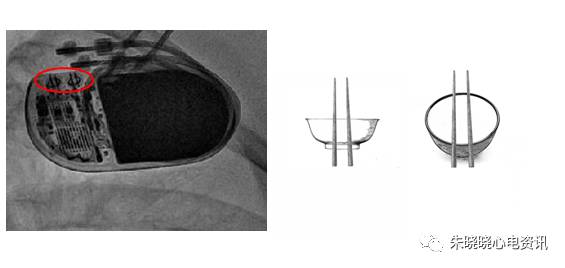

百多力起搏器接线部分和餐桌上的碗筷组合相似(图11),

图11 百多力起搏器